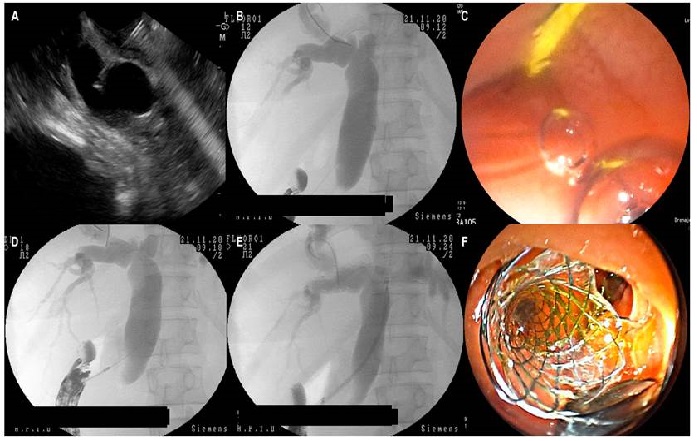

Bajo visión endosonográfica se identifica el conducto biliar y se delimita el nivel de la obstrucción biliar. Luego se realiza la medición del tamaño del conducto, además de la distancia del transductor a la pared más proximal al equipo. En todos los casos se utiliza el Doppler para evitar vasos sanguíneos. Posteriormente, se procede a la punción del colédoco con aguja de 19 G bajo visión endosonográfica, se aspira para verificar que haya retorno de bilis y luego se aplica un medio de contraste hidrosoluble para realizar una colangiografía que se verifica fluoroscópicamente. Una vez realizado el mapa de la vía biliar, se avanza la guía hidrofílica de 0,035 pulgadas, se retira la aguja de forma coordinada para evitar la salida de la guía del conducto biliar. Bajo visión endosonográfica y fluoroscópica se pasa el cistotomo con corte puro a 70 W hasta acceder a la vía biliar, de inmediato se retira el cistotomo y se avanza un stent biliar metálico cubierto hasta posicionarlo en visión fluoroscópica y endoscópica, y finalmente se identifica un efectivo drenaje biliar (Figura 1).